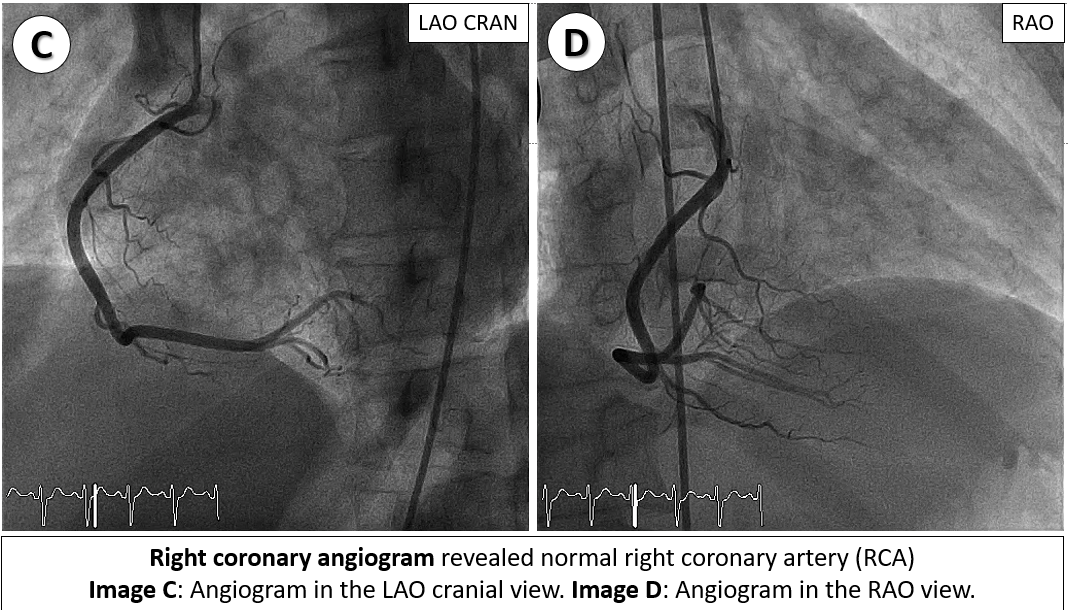

Emergency coronary angiography revealed a critical ostial left main stenosis with TIMI 2 flow and a normal right coronary artery. Following engagement with 6-Fr JL 4.0 side-hole catheter, sequential pre-dilatation was performed using 3.5x15 mm and 4.5x15 mm non-compliance (NC) balloons. A 4.0x12 mm drug-eluting stent was deployed in the left main artery, followed by post-dilatation with a 4.5x15 mm NC balloon. Subsequently, an intra-aortic balloon pump was inserted for hemodynamic support.